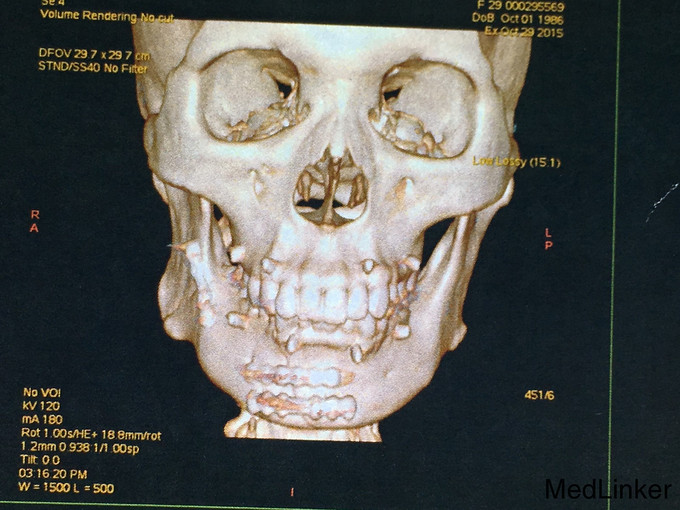

查体:神志清楚,右下颌体部见长约2.0cm开放创口,张口度1.5cm,咬合关系紊乱,右下唇麻木感,43,44间见明显骨折线,异常动度,48松动II,牙龈撕裂,右下颌肿胀,右侧髁状突冲击试验减弱,上颌骨无异常动度,于无异常。 辅查:CT,右下颌骨颏部及下颌角不骨折。

诊断:右下颌骨颏部及下颌角不骨折 治疗:右下颌骨颏部及下颌角部骨折经口内切开复位内固定。